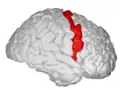

Precentral gyrus | |

![]() Precentral gyrus a prominent gyrus of the frontal lobe | |

The precentral gyrus is a prominent gyrus on the surface of the posterior frontal lobe of the brain. It is the site of the primary motor cortex that in humans is cytoarchitecturally defined as Brodmann area 4.

The precentral gyrus lies in front of the postcentral gyrus - mostly on the lateral (convex) side of each cerebral hemisphere - from which it is separated by the central sulcus. Its anterior border is represented by the precentral sulcus, while inferiorly it borders to the lateral sulcus (Sylvian fissure). Medially, it is contiguous with the paracentral lobule.